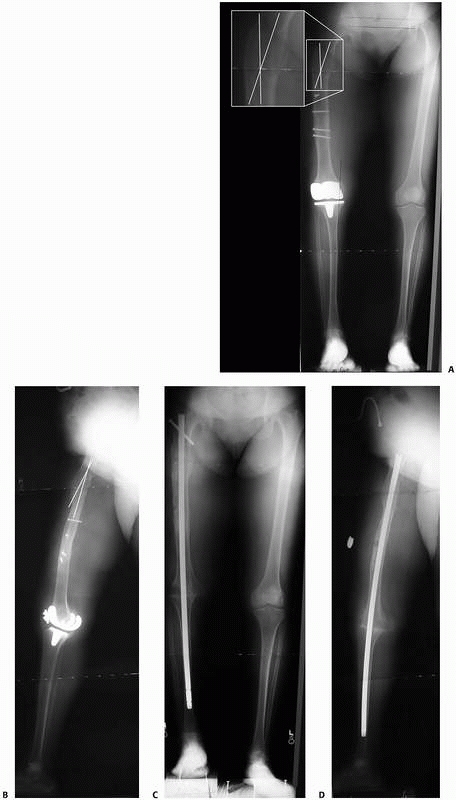

FIGURE 26-23 A,B.

AP and lateral 51-inch alignment radiographs of a 52-year-old woman with a painful total knee arthroplasty. This patient had severe arthrofibrosis, severe pain, and had failed revision total knee arthroplasty. She was referred for a knee fusion but was noted to have an oblique plane angular malunion of her proximal femur from a prior fracture, as indicated by the white lines superimposed on the femur. It was felt that without correction of this femoral malunion, passage of the knee fusion nail through the angled femoral diaphysis would have been difficult, and the final clinical and functional results would likely have been suboptimal due to malalignment of the mechanical axis of the lower extremity. C,D. Follow-up radiographs 5 months after operative treatment with resection of the total knee arthroplasty, percutaneous corticotomy of the proximal femur to correct the deformity, and percutaneous antegrade femoral nailing to stabilize the corticotomy site and stabilize the knee fusion site. |

the lower extremity because of the strength and load-sharing

ideal for cases where diaphyseal deformities are being corrected (Fig. 26-23).